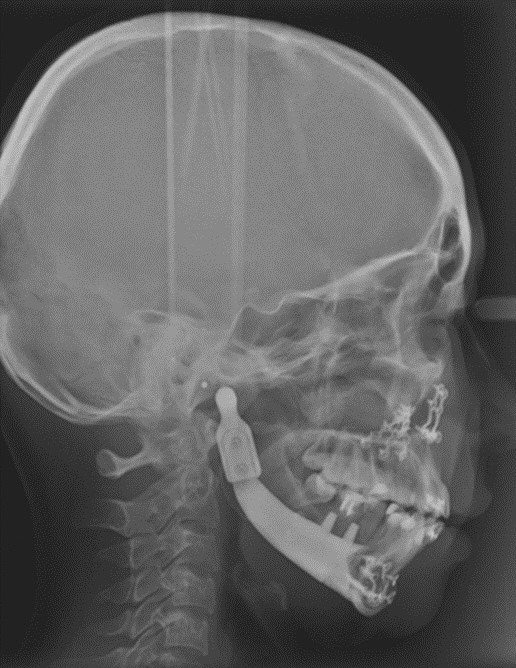

해당 기술은 하악골의 결손 부위에 삽입되는 환자 맞춤형 하악골 임플란트입니다. 개인 맞춤형 3D 프린팅 기술을 이용해 손쉽고 빠르게 제작할 수 있으며, 아래턱뿐만 아니라 턱뼈와 함께 손실된 치아를 복원하는 기술도 동시에 적용 가능합니다.

이번에 미국 특허로 등록된 ‘하악골 결손 부위에 삽입되는 환자 맞춤형 하악골 임플란트’는 사고로 인한 외상 혹은 구강암 등으로 아래턱뼈가 결손된 환자에게 본인 구강구조와 일치하는 맞춤형 인공 턱뼈를 제공할 수 있습니다. 추후 치과용 임플란트를 식립할 수 있으며 치아 기능까지 회복할 수 있습니다.